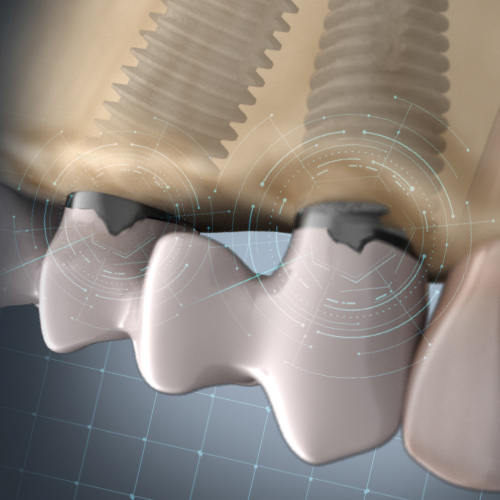

Dental Rehabilitation of the Atrophic Maxilla

This Compendium eBook features a continuing education (CE) article presents important diagnostic and treatment planning principles of the All-on-4 treatment concept for the rehabilitation of the atrophic maxillary arch, and includes a case report illustrating free-hand implant placement using this treatment approach.

Implantology Solutions

This Compendium eBook offers a continuing education (CE) article that examines treatment planning for full-arch reconstruction with implant overdentures. A long-term case report is also featured in this eBook, highlighting the steps involved in a full-arch reconstruction using transitional ...

Planning Full-Arch Reconstructions for Today and Tomorrow: Implant Overdentures and Fixed Restorations

Thursday, September 30, 2021